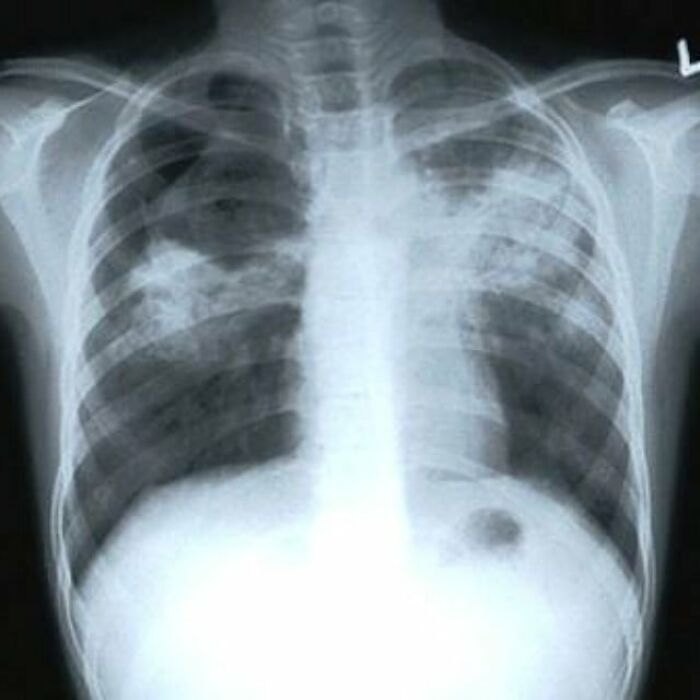

Active Pulmonary Tb, Infiltrates Or Consolidations And/Or Cavities Are Often Seen In The Upper Lungs With Or Without Mediastinal Or Hilar Lymphadenopathy